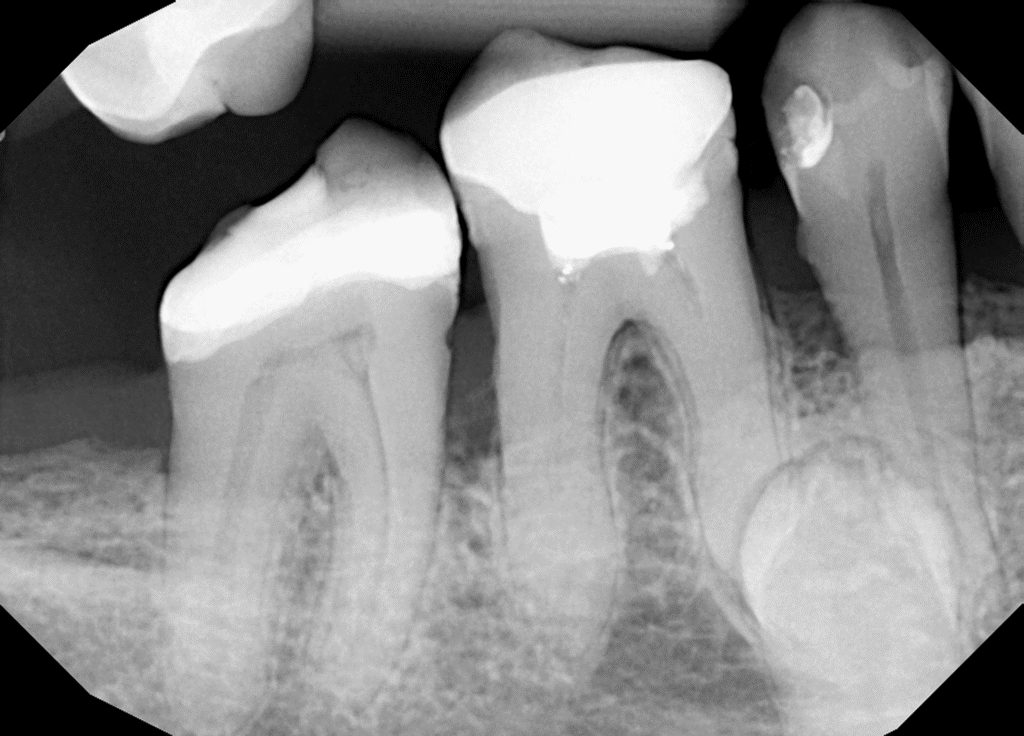

Pacjentka lat 54 trafiła do mojej kliniki skierowana z innego gabinetu celem leczenia endodontycznego zęba 46. W badaniu stwierdziłem znaczny zanik światła kanału korzeniowego. W badaniu tomograficznym stwierdziłem całkowity zanik kanału korzeniowego w strefie mezjalnej. Korzeń dystalny mimo widocznego światła kanału na CBCT, widoczne było wiele zwapnień w środkowej części kanału. Po wykonaniu dostępu endodontycznego zlokalizowałem materiał wypełniający kanał pozostawiony po poprzednim nieskutecznym leczeniu endodontycznym. Do usunięcia wykorzystałem laser 2780nm (25mJ/puls). W kolejnych etapach instrumentacji wspomaganie ultradźwiękami oczyściłem strefy mezjalną i dystalną. Instrumentacja themo-

mechaniczna polegała na zastosowaniu protokołu ciągłej chelacji wraz z użyciem lasera

2780nm z końcówką płaską (50mJ/puls) celem udrożnienia przestrzeni endodontycznych. Po wstępnym uzyskaniu drożności zastosowałem instrumentację maszynową wspomagająco celem udrożnienia przestrzeni. Finalnie obturacja z zastosowaniem ćwieków gutaperkowych kalibrowanych na WL i uszczelniacza na bazie krzemianów wapnia. W przeciwieństwie do tradycyjnych uszczelniaczy, nie wymaga mieszania, co eliminuje błędy w proporcjach i zapewnia powtarzalną konsystencję. Jest materiałem wysoce biokompatybilnym i bioaktywnym. Finalnie zamknięto ząb odbudową kompozytową tymczasową i skierowano na dalsze leczenie protetyczne do gabinetu kierującego pacjenta.